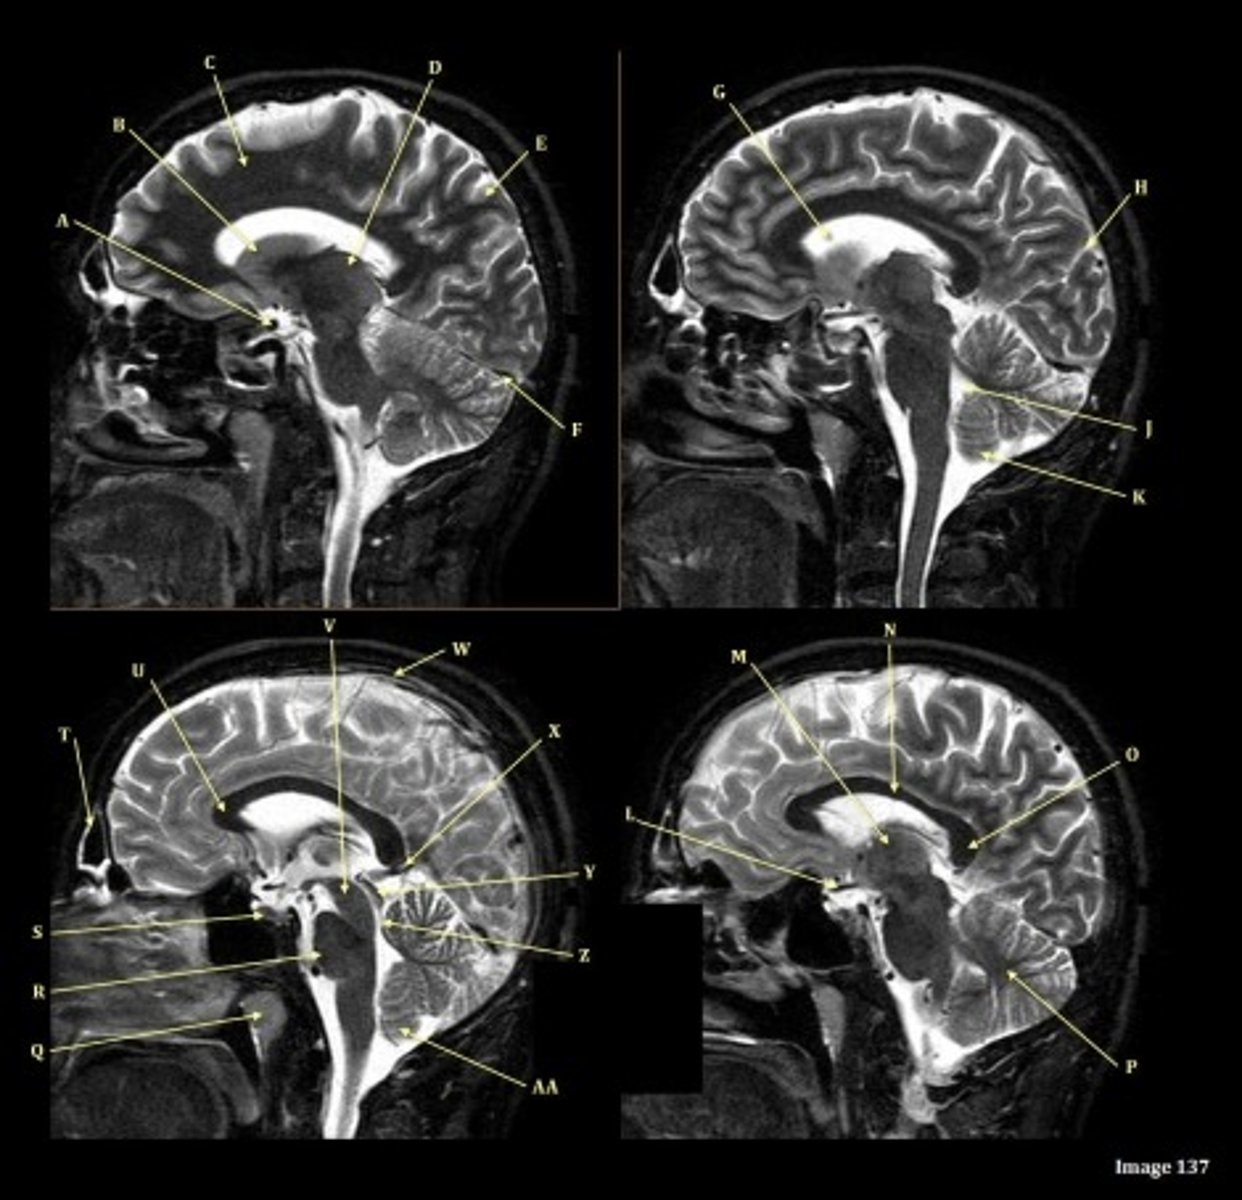

What type of sequence?

T2 FLAIR; Sagittal

A FLAIR (Fluid Attenuated Inversion Recovery) sequence is utilized to suppress signal from cerebrospinal fluid (CSF).

T1, sagittal

A- region

Genu of Corpus Callosum

B- region

Splenium of Corpus Callosum

C

pons

D

cerebellum

A

lateral ventricle

B

corpus callosum

thalamus

D- separates what

tentorium cerebelli- cerebrum (occipital and temporal lobes) from brainstem and cerebellum

E

fourth ventricle

F

medulla oblongata

caudate nucleus

third ventricle

lentiform nucleus

frontal sinus

pituitary gland

corpus

fornix

internal carotid artery